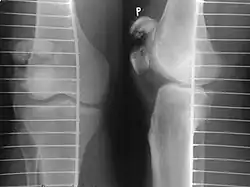

Diagnosis is based on symptoms and confirmed with X-rays.[3] In children an MRI may be required.[3]

Some people have a normal bipartite patella or two-part patella which can appear as a fracture. The fragment is usually seen in the top outer corner of the patella and can be distinguished from a fracture by being present in both knees.[6]